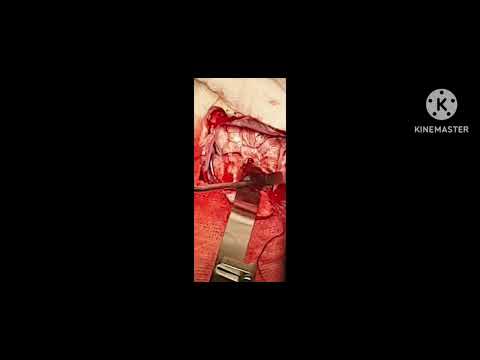

Hellow guys, Welcome to my website, and you are watching COLLOID CYST 3RD VENTRICLE NAVIGATION GUIDED MICROSURGERY -dr suresh dugani/HUBLI/INDIA. and this vIdeo is uploaded by drsuresh dugani NEUROSURGERY EDUCATIVE VIDEOS ATLAS at 2017-07-11T09:30:43-07:00. We are pramote this video only for entertainment and educational perpose only. So, I hop you like our website.